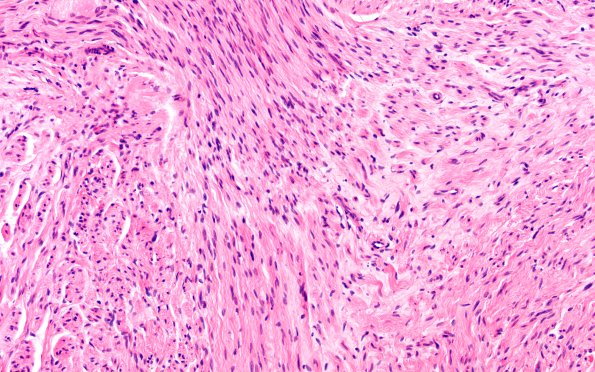

Washington University Experience | PERIPHERAL NEUROPATHY | 19 TRAUMATIC INJURIES | 1A5 Neuroma, traumatic (Case 1) H&E 20X

Notice that there are other histologic appearances with a different more confused proliferation of elements in this neuroma consisting of irregular fibrous connective tissue admixed with axons. (H&E)